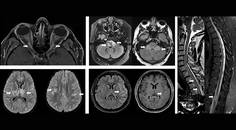

MS Minute: Myelin Oligodendrocyte Glycoprotein Antibody–Associated Disease

Cristina Valencia-Sanchez, MD, PhD; Dean Wingerchuk, MDCristina Valencia-Sanchez, MD, PhD; Dean Wingerchuk, MD - MS & Immune Disorders